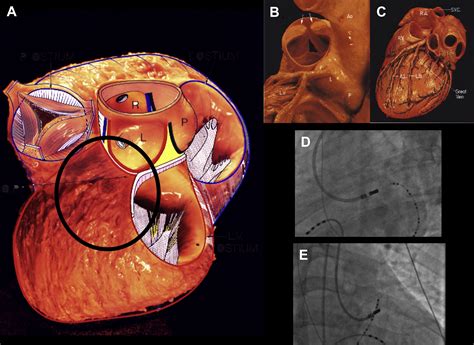

Svt Heart Ablation is a medical procedure designed to correct abnormal heart rhythms, specifically those associated with supraventricular tachycardia. This condition occurs when the electrical signals in the heart’s upper chambers (atria) are disrupted, leading to a rapid and irregular heartbeat. The ablation process involves using energy, typically radiofrequency or cryoenergy, to create small scars in the heart tissue that disrupt the abnormal electrical pathways, thereby restoring a normal heart rhythm.

Svt Heart Ablation is typically performed in a catheterization laboratory under local anesthesia. The procedure involves several key steps:

• Catheter Insertion: Thin, flexible tubes called catheters are inserted into a blood vessel, usually in the groin or neck, and guided to the heart.

• Electrical Mapping: The catheters are used to map the electrical activity of the heart, identifying the precise location of the abnormal pathway.

• Energy Application: Once the abnormal pathway is located, energy is applied to create small scars, effectively disrupting the pathway.

• Monitoring: The heart’s electrical activity is continuously monitored to ensure the abnormal rhythm has been eliminated.